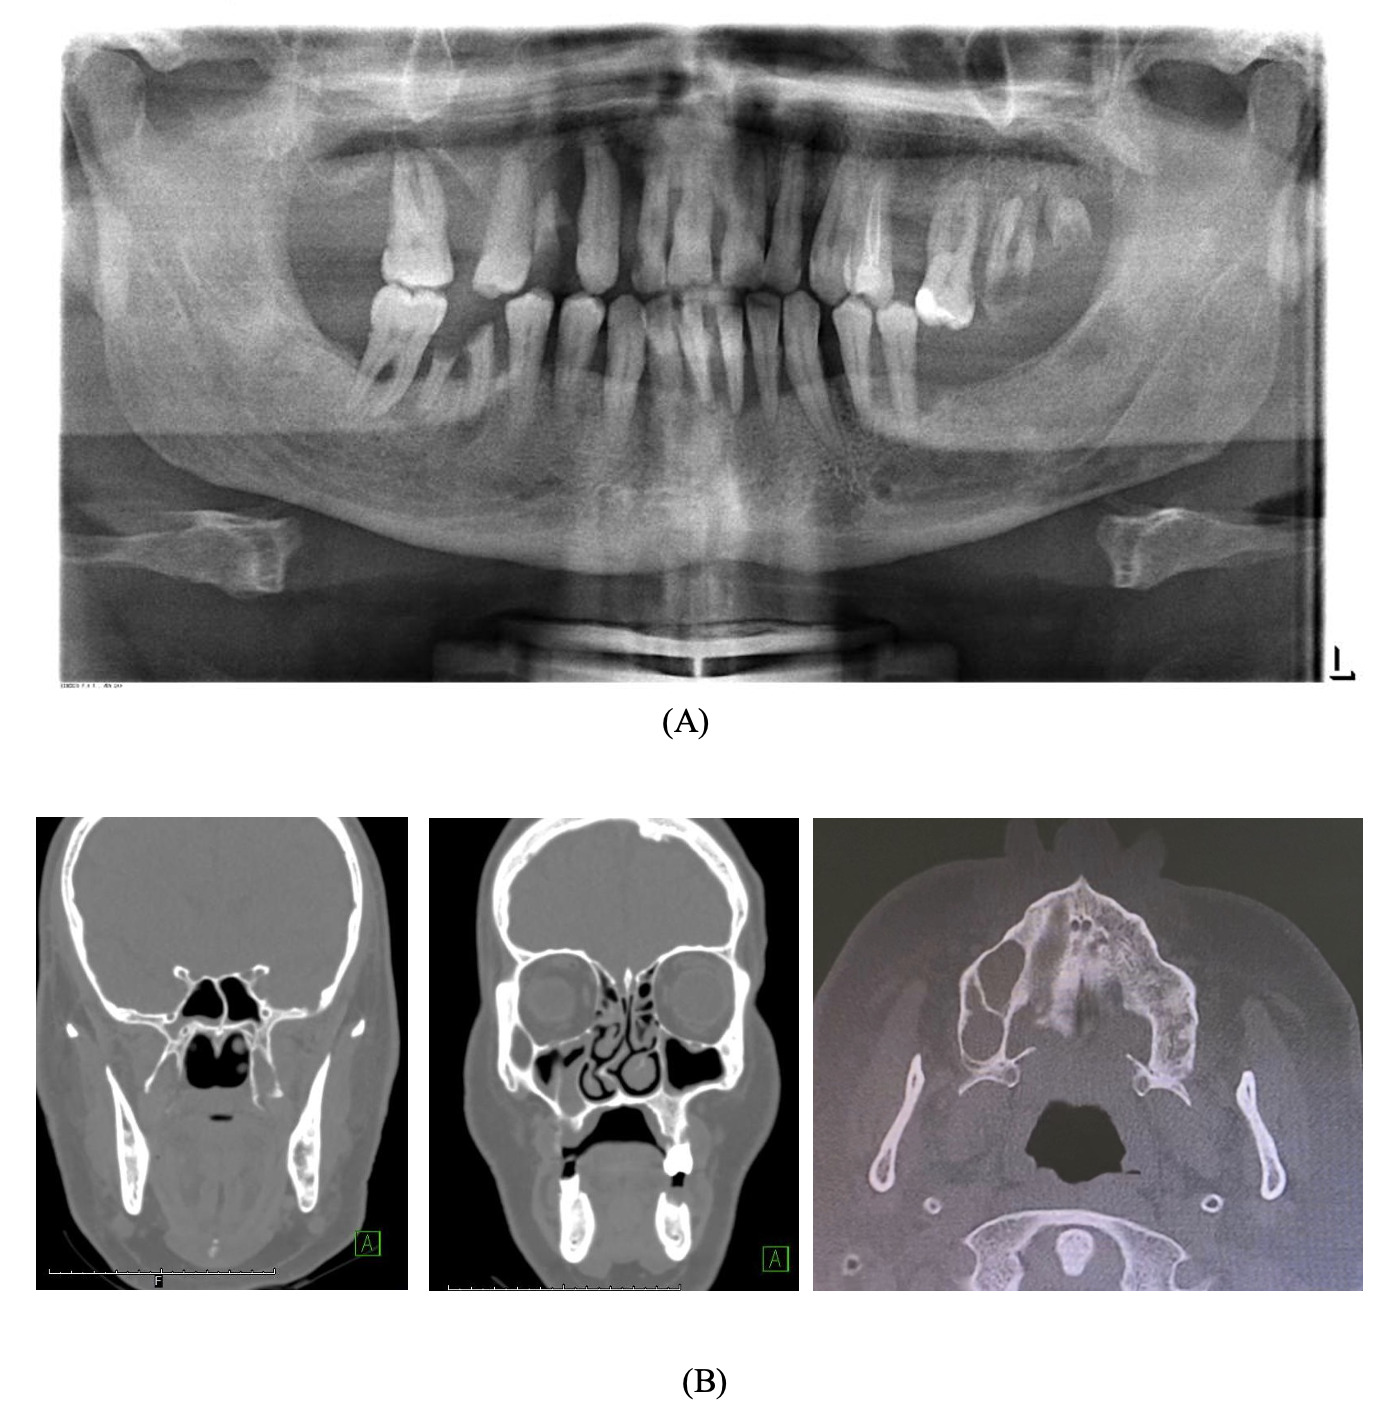

A pre-operative orthopantomogram (OPG) showed multiple non-restorable teeth in both jaws, as well as generalised, horizontal moderate to severe bone loss (Figure 2a). Pre-operative cone beam computed tomography (CBCT) showed an ill-defined lesion on the palatine process of the right maxillary and alveolar bone (Figure 2b).